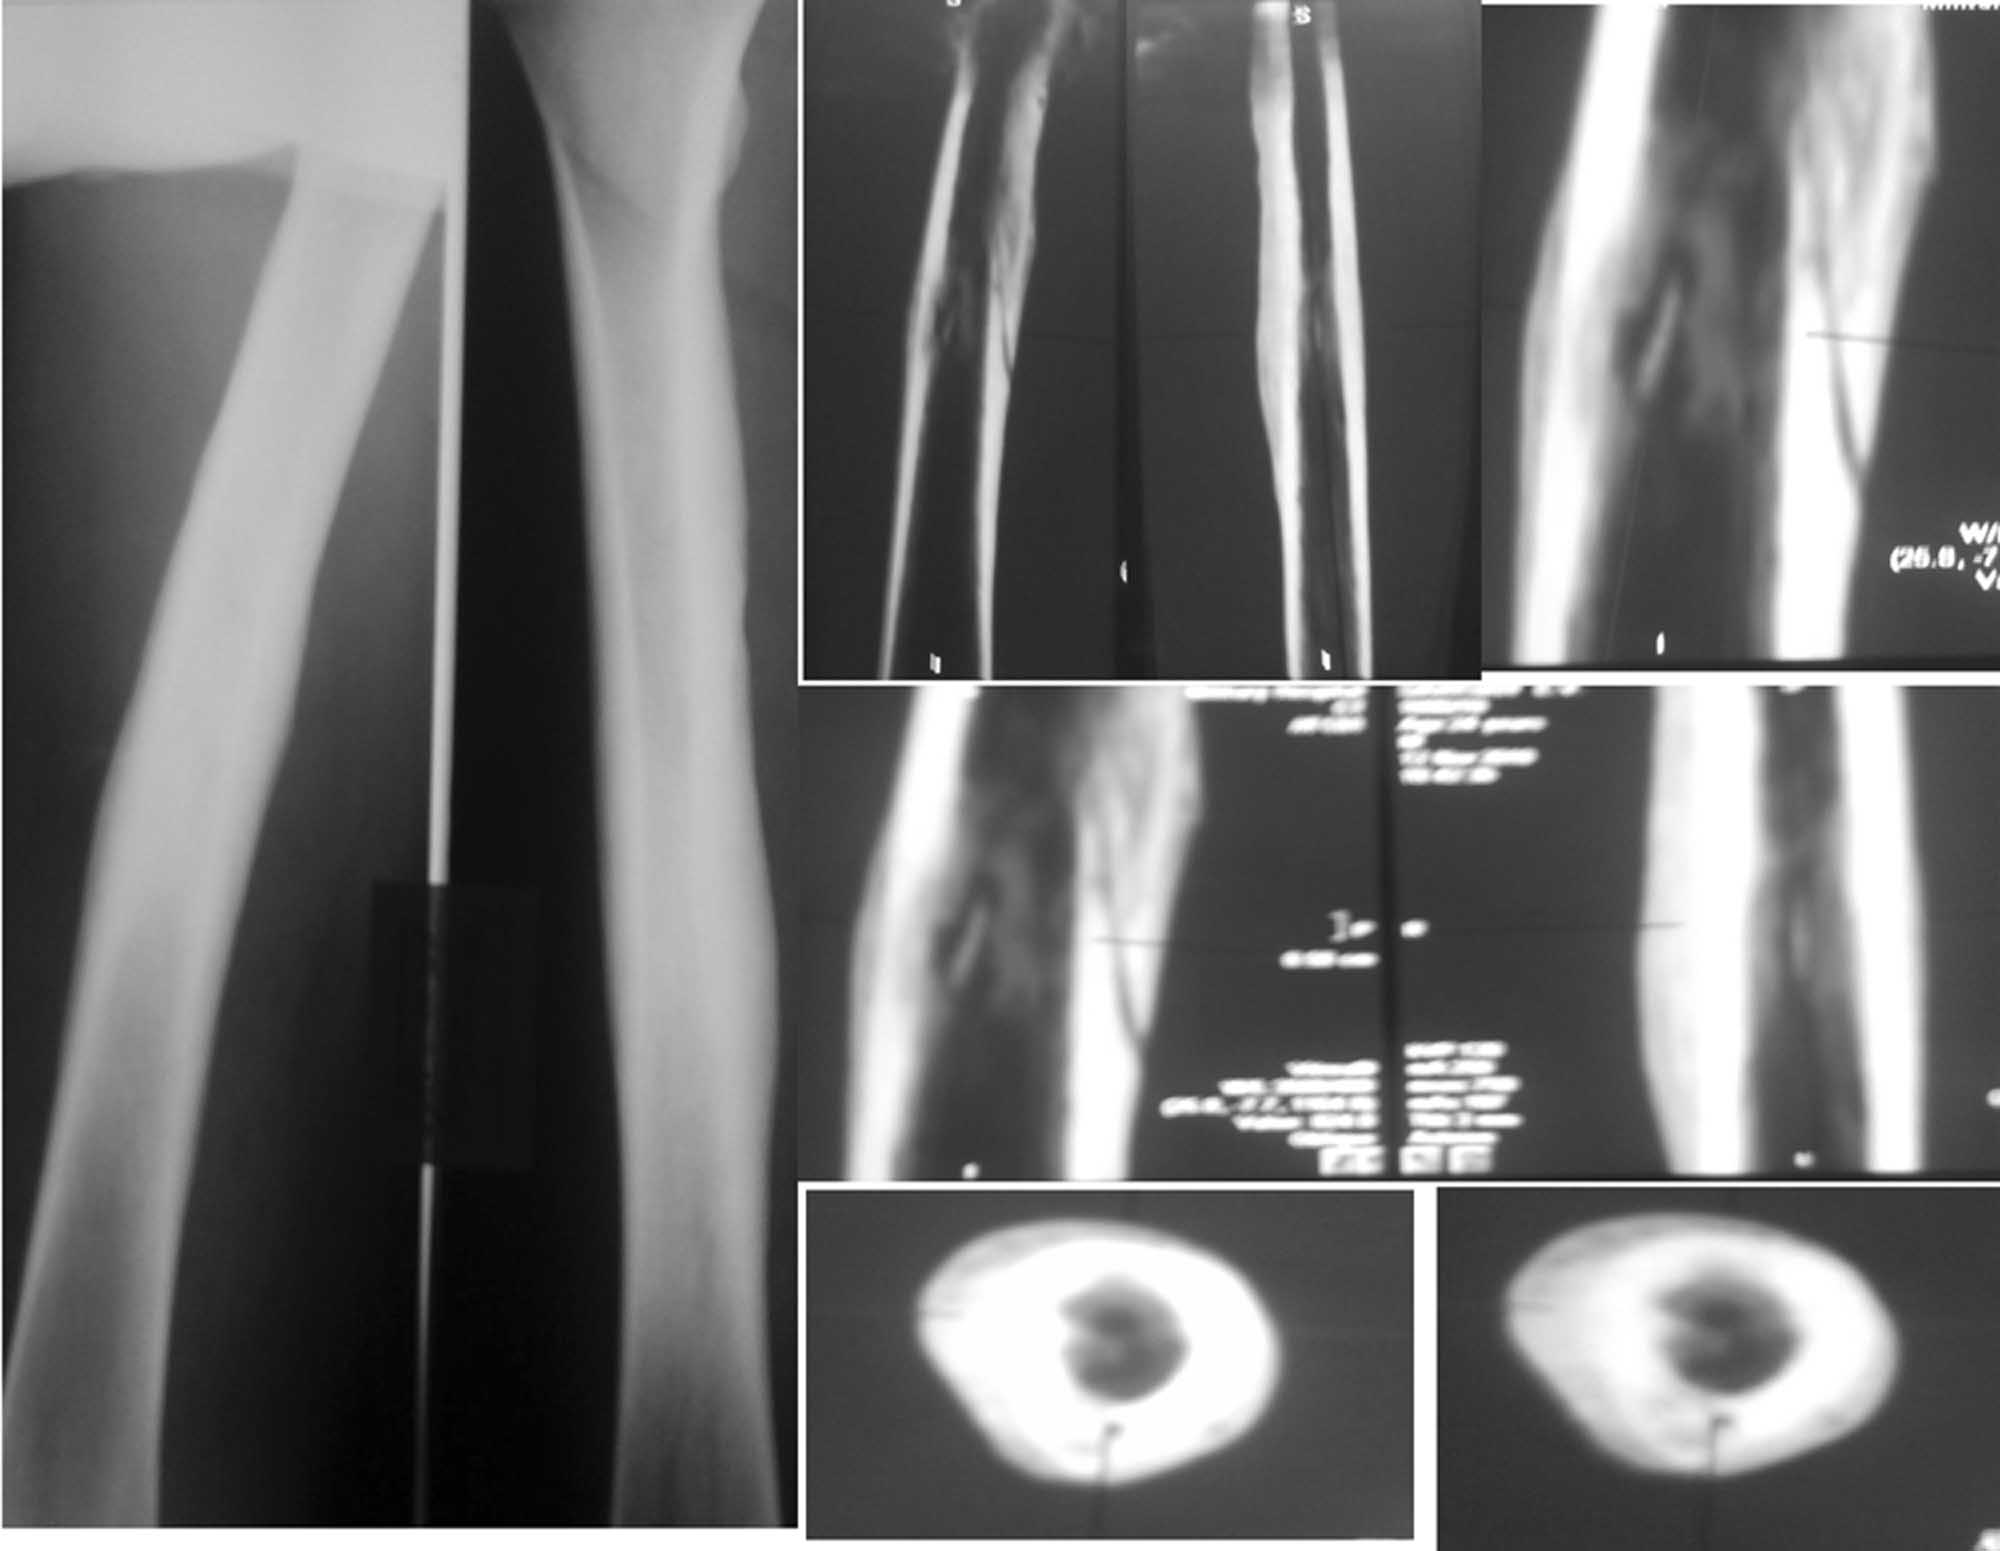

Случай «вялотекущего» гематогенного остеомиелита у молодого пациента

Пациенту 24 года. Беспокоят умеренные боли в области нижней трети правого бедра при нагрузках и ограничение сгибания правого коленного сустава. В покое, в т.ч. ночью, болей нет.

2 года назад без видимой причины появились боли и припухлость в нижней трети правого бедра. Был госпитализирован в отделение гнойной хирургии с диагнозом «Воспалительный инфильтрат». Рентгенограммы бедра в тот период патологии не выявили. На фоне а/б терапии цефазолином инфильтрат разрешился полностью.

Последующие 2 года ничего не беспокоило. Около 2 недель назад появились боли и припухлость в нижней трети правого бедра, вновь без видимой причины. На рентгенограммах бедра выявлены выраженная периостальная реакция, на КТ признаки хронического гематогенного остеомиелита.

Объективно: внешне мягкие ткани бедра не изменены, следов от свищей нет, умеренно болезненна область нижней трети правого бедра по медиальной поверхности, без изменения кожной температуры, признаков инфильтрации и флюктуации. Ограничено сгибание в правом коленном суставе до 90 гр из-за болей.

Лабораторные данные без особенностей за исключением СОЭ – 25 мм в час, уровень СRP в 2 раза выше нормы.

Моё мнение, что это хронический(гематогенный) остеомиелит правого бедра в ср. трети, секвестральная, безсвищевая форма. возможно происходит формирование ещё и секвестра наружного кортикала.

Объём операции - щелевидная трепанация по наружной поверхности, через изменённый кортикал, секвестрнекрэктомия, остеопластика остаточной полости из гребня подвздошной кости(трансплантант фрагментировать некрупно и плотно импактировать в остаточную полость)и дренирование с подведением ирригатора для антибиотиков. Возможно и мышечная пластика на проксимальной ножке. в послеоперационном периоде гипсовая иммобилизация до4-х недель.